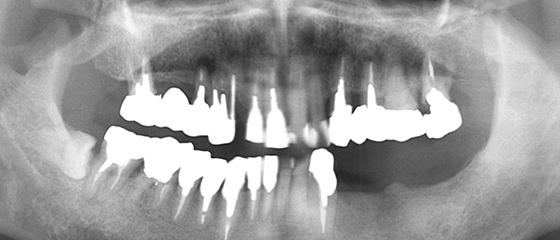

治療前の状態

糖尿病で内科に通院しており、なおかつ喫煙を止めることが出来ない患者さんです。インプラントにとって、糖尿病と喫煙習慣は大敵です。レントゲンを見ても、状態の良い歯はありません。